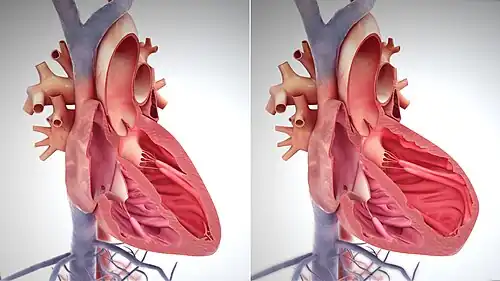

Heart failure is caused by any condition that reduces the efficiency of the heart muscle, through damage or overloading. Over time, these increases in workload, which are mediated by long-term activation of neurohormonal systems such as the renin–angiotensin system and the sympathoadrenal system, lead to fibrosis, dilation, and structural changes in the shape of the left ventricle from elliptical to spherical.[23]

The heart of a person with heart failure may have a reduced force of contraction due to overloading of the ventricle. In a normal heart, increased filling of the ventricle results in increased contraction force by the Frank–Starling law of the heart, and thus a rise in cardiac output. In heart failure, this mechanism fails, as the ventricle is loaded with blood to the point where heart muscle contraction becomes less efficient. This is due to the reduced ability to cross-link actin and myosin myofilaments in over-stretched heart muscle.[58]

Several terms are closely related to heart failure and may be the cause of heart failure, but should not be confused with it. Cardiac arrest and asystole refer to situations in which no cardiac output occurs at all. Without urgent treatment, these events result in sudden death. Myocardial infarction (heart attack) refers to heart muscle damage due to insufficient blood supply, usually as a result of a blocked coronary artery. Cardiomyopathy refers specifically to problems within the heart muscle, and these problems can result in heart failure.[68] Ischemic cardiomyopathy implies that the cause of muscle damage is coronary artery disease. Dilated cardiomyopathy implies that the muscle damage has resulted in enlargement of the heart.[69] Hypertrophic cardiomyopathy involves enlargement and thickening of the heart muscle.[70]

An echocardiogram (ultrasound of the heart) is commonly used to support a clinical diagnosis of heart failure. This can determine the stroke volume (SV, the amount of blood in the heart that exits the ventricles with each beat), the end-diastolic volume (EDV, the total amount of blood at the end of diastole), and the SV in proportion to the EDV, a value known as the ejection fraction (EF). In pediatrics, the shortening fraction is the preferred measure of systolic function. Normally, the EF should be between 50 and 70%; in systolic heart failure, it drops below 40%. Echocardiography can also identify valvular heart disease and assess the state of the pericardium (the connective tissue sac surrounding the heart). Echocardiography may also aid in deciding specific treatments, such as medication, insertion of an implantable cardioverter-defibrillator, or cardiac resynchronization therapy. Echocardiography can also help determine if acute myocardial ischemia is the precipitating cause, and may manifest as regional wall motion abnormalities on echo.[71]